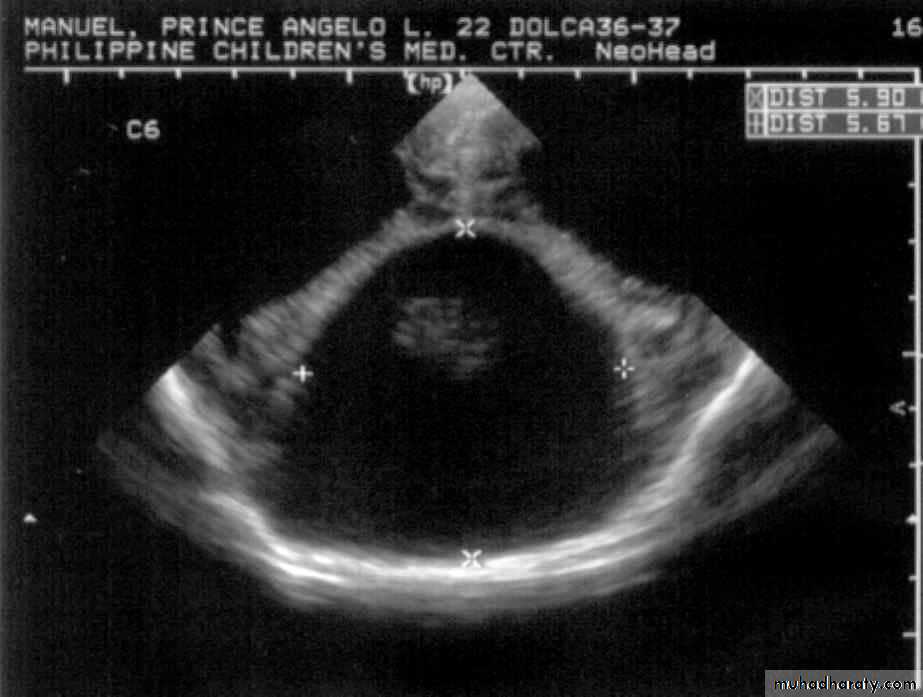

P.M, 22 days old CA 36-37 wks, with cleft lip and palate

Holoprosencephaly, semilobarMacrogyria

Absent Septum Pellucidum

Dysgenesis of the Corpus Callosum